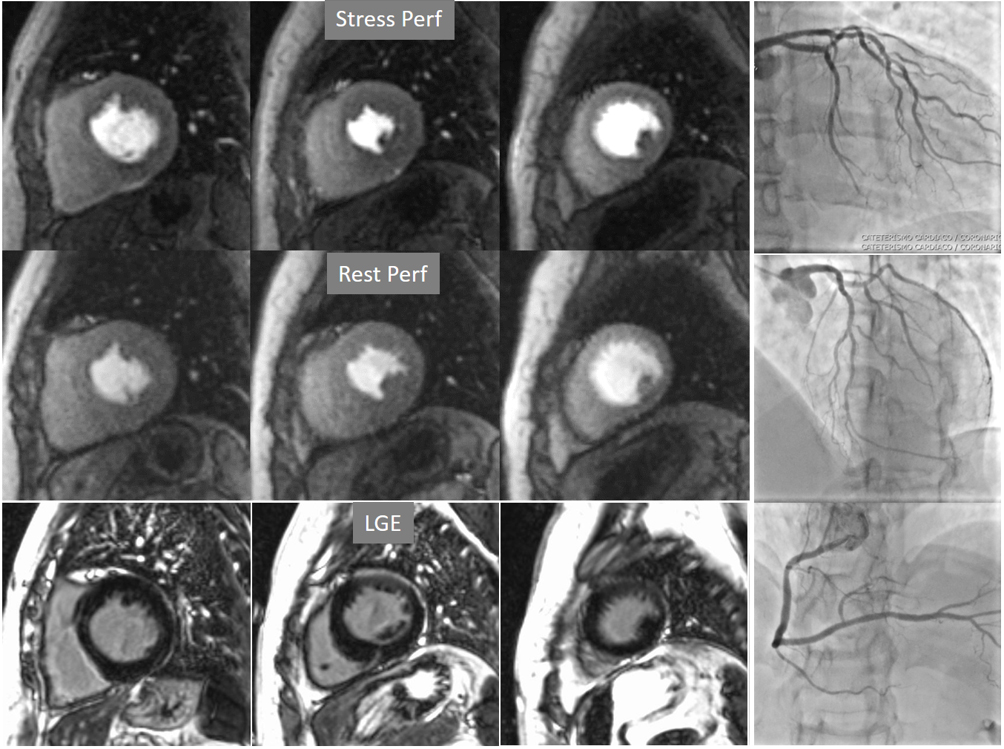

The most immediate and commonest method of analysis is the visual detection of a distinctive deficient increase in signal intensity of a region of the left ventricular myocardium during the first passage of a CA bolus under vasodilatory conditions lasting for at least 3 consecutive frames of the sequence. This perfusion defect should not be present at rest and should not correspond to an area of previous MI. The detection of such a defect is assumed to be due to a reduction in CFR of this territory which, when attributed to a particular coronary artery [39], allows for the conclusion of the presence of a significant epicardial stenosis in the vessel (Fig. 6).

Fig. 6.Single-vessel perfusion defect. Extensive subendocardial perfusion defect at the antero-septal region (arrow, on the upper left panel) not present at rest, in a region without LGE (lower left panel). Angiography proves this defect to be due to a tight stenosis of the LAD coronary artery (arrow, on the lower right panel).

Criteria for an appropriate interpretation of dark, unenhanced regional myocardial signals as due to perfusion defects have been issued by scientific societies [40]. According to these recommendations, it is accepted that a true defect (1) appears when contrast arrives at the left ventricular myocardium, (2) persists for several cardiac cycles, (3) is not restricted to a thin linear contour, (4) it is more prominent at the subendocardial level, extending variably through the whole thickness of the myocardium, (5) it is not present at rest, and (6) corresponds to a distribution territory of a coronary artery.